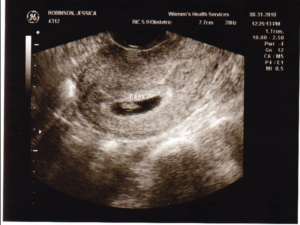

Узи на 5 неделе беременности

УЗИ на пятой неделе беременности покажет: размеры матки, количество плодных яиц и место, где локализуется плод в матке.

Уже на пятой неделе начинает работать сердечно — сосудистая система, поэтому грамотный специалист в ходе ультразвукового исследования, путем сопоставления сердечного ритма и двигательной активности плода, сможет оценить и спрогнозировать его жизнедеятельность.

Врачи не рекомендуют делать УЗИ на 5 неделе беременности, так как срок еще слишком мал, чтобы исследование было достаточно информативным. Если же вы одна из тех нетерпеливых будущих мам, которые уже записались на УЗИ на 5 неделе, то вы можете узнать следующие новости:

- Где расположено плодное яйцо. В норме плодное яйцо на 5 неделе беременности расположено в полости матки. Если врач обнаруживает плодное яйцо вне матки (в маточной трубе или в другом месте), то говорят о внематочной беременности.

- Если у вас двойня, то уже на 5 неделе беременности УЗИ скорее всего сможет это показать.

- Размеры плодного яйца: по этому показателю врач уточняет срок беременности. Размеры плодного яйца на 5 неделе могут варьировать от 6 мм до 18 мм.

- Есть ли сердцебиение. В норме сердце эмбриона начинает биться на 5 неделе беременности, однако не все аппараты УЗИ способны зарегистрировать сердечную активность на этом сроке. Вагинальное УЗИ в этом случае более чувствительно и чаще выявляет сердцебиение на 5 неделе. Не расстраивайтесь, если УЗИ на 5 неделе не показало сердцебиения – это еще не говорит о замершей беременности. Вам необходимо пройти УЗИ повторно через 1-2 недели.

УЗИ

Если будет назначено УЗИ на 5 неделе беременности, то исследование позволит определить место прикрепления эмбриона в матке, а к концу недели можно будет разглядеть и сердцебиение.

Совет! Если срок беременности перевалил за 5 недель и при проведении УЗИ сердцебиение не было выявлено, то это не означает, что развитие малыша идет неправильно. Скорее проблема в возможностях оборудования для проведения исследования.